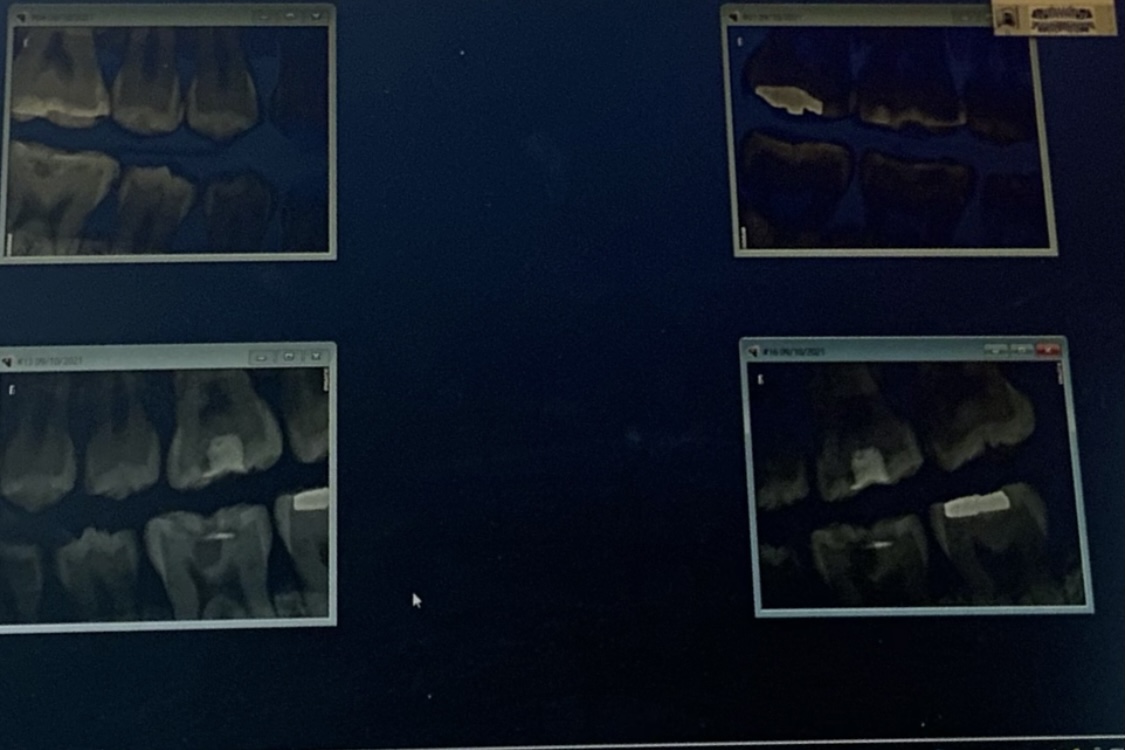

두둥-! 제 치아 사진 공개합니다..

잘 안보이는데 어디가 어딘지도 모르겠는데 한장 찍어봤어요

예전부터 충치 치료한게 많아서 이곳저곳에 보이네요